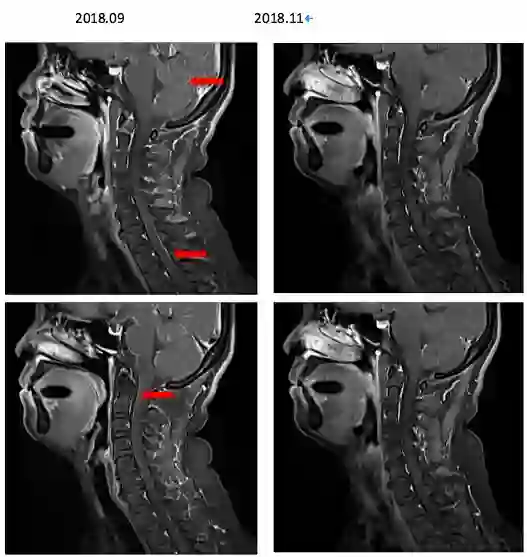

患者于2018年9月27日因“剧烈头痛伴呕吐”就诊于我科——郑州大学附属第一医院肿瘤科,查体急性病容,表情痛苦,神志清楚,脑膜刺激征可疑阳性,考虑脑膜转移性可能性大,故立即行腰椎穿刺,提示颅内压400mmH2O,并行脑脊液细胞学检查 ,未见肿瘤细胞。但是结合患者症状体征仍不能排除脑膜转移可能。故行颈椎增强MRI排除其他部位脑脊液转移可能,检查结果提示颈椎增强MRI可见脑脊膜多发转移(图6)。

图6. 颈椎增强MRI提示脑脊膜多发转移影像

图7.治疗后复查患者颈椎核磁影像